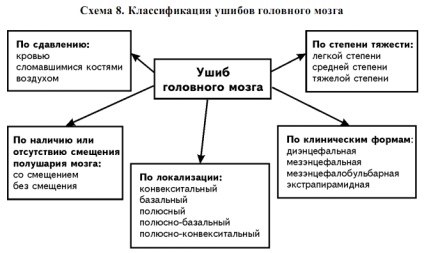

Atunci când diagnosticul este o diviziune a numărului și mărimii daunei:

- contuzie cerebrală, severă - formă, ceea ce duce, conform statisticilor, până la aproximativ 50% din decesele in traumatism cranian. Pacienții cu acest diagnostic reabilitată în cursul anului, și nu întotdeauna până la capăt;

- contuzii cerebrale moderate, adesea combinate cu o bază și o fractură a bolții craniene, sângerări la ruptura de anevrism;

- contuzie cerebrală ușoară - TBI cu consecințe favorabile și reînnoirea în continuare a sănătății vătămate, nu poartă pericolul vieții sale.